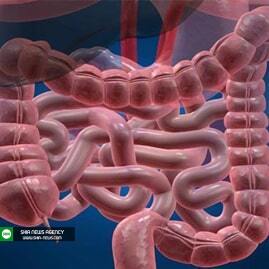

به گزارش «شیعه نیوز»، علی هادیانپور اظهار کرد: انسداد روده بزرگ باعث میشود گاز یا مدفوع نتواند از بدن خارج شود و میتواند در هر قسمتی از آن رخ دهد.

وی عنوان کرد: روده بزرگ بخشی از سیستم گوارش است که شامل کولون و رکتوم میشود، روده بزرگ نقش حیاتی در دفع ضایعات از بدن دارد، تفالههای غذایی مایع از روده باریک وارد روده بزرگ شده و در آنجا تبدیل به جامد میشوند.

هادیانپور در پاسخ به این سؤال که انسداد روده بزرگ چقدر شایع است؟، بیان کرد: انسداد روده بزرگ ۲۰ درصد از کل موارد انسداد روده را شامل میشود اما انسداد روده باریک شایعتر است.